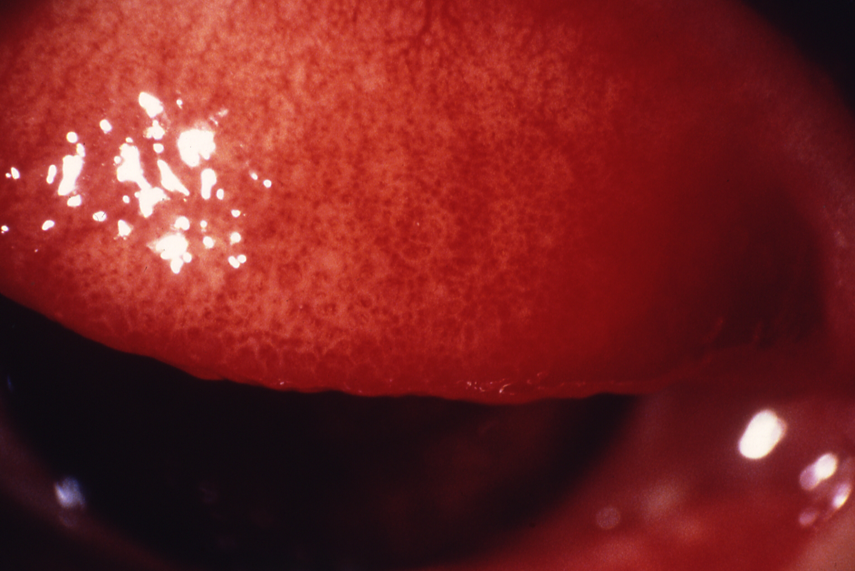

図12 クラミジアによる濾胞性結膜炎

結膜円蓋部を中心に大型の充実性濾胞が多数みられる。クラミジア結膜炎の成人例。アデノウイルス結膜炎との鑑別が必要である。